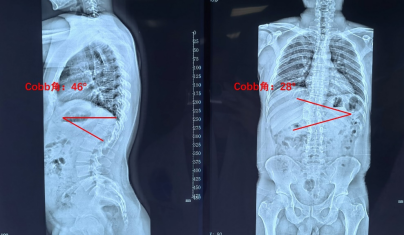

术前全脊柱全长X线正侧位示:胸椎后凸Cobb角46°;侧凸Cobb角28°;CT三维重建示:胸11、胸12蝴蝶椎异常发育

术前术后全脊柱正侧位X线